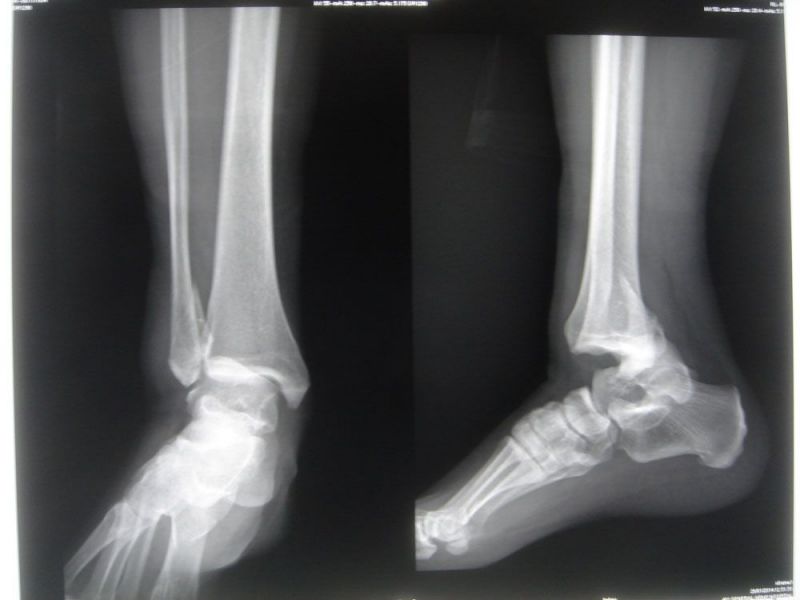

Ankle fracture-dislocation- Open reduction internal fixation (A-P view in theater)